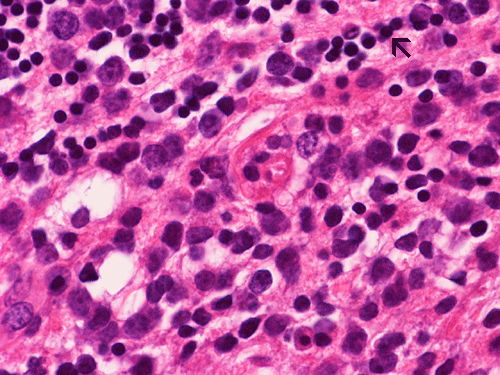

The material for permanent sections is largely semi-liquid in consistency. There are only very few fragments of cerebellar tissue that are infiltrated by the tumor. The bulk of the diagnostic material are solid sheets of neoplastic cells (Panel G). The cytologic features are similar to what we have observed in the cytologic preparation  (Panel H). In essence, the tumor is composed of solid sheets of large polygonal and rather monotonous atypical cells with a thin rim of cytoplasm and molding which lead to a mosaic pattern. These features are consistent with lymphoma. On immunohistochemistry, practically all the neoplastic cells are positive for leukocyte common antigen (LCA) (Panel I), CD20 (Panel J) and many of them are positive for CD79a (Panel K). Only reactive T-cells but not the large, atypical cells are positive for CD3 (Panel L). The neoplastic cells are essentially negative for Bcl-6 (Panel M) but some of them are positive for Bcl-2 (Panel N). The large atypical cells are negative for kappa and lambda light chains on immunohistochemistry. There is no immunoreactivity in the neoplastic cells for cytokeratin (AE1/AE3), S100, pan-melanoma marker (Mart-1, tryptase, and HMB-45).

Similar to the systemic counterparts, diffuse large-B cell lymphomas of the CNS are characterized by large, pleomorphic lympyoid cells. Histologically, however, PCNSL shows the unique angiocentric infiltrating pattern, which is more prominent at the edge of the lesion. The tumor cells dissect and expand the perivascular network in a concentric manner which is best demonstrated by reticulin stain

[click here to see a picture]. Systemic DLBCL does not show this particular pattern of growth. The tumor infiltrates the brain parenchyma between blood vessels as small clusters and individual cells. Confluent areas of tumor may show necrosis, with residual viable tumor cells being found mostly around blood vessels. The boundary of the tumor may be relatively discrete, but it is more common for perivascular cuffs and single infiltrating lymphoma cells to be found at some distance from the tumor mass, extending far away from radiographically evident tumor margins. The malignant lymphocytes lack a cohesive appearance, do not form glands or other structures. The nuclei vary from round to indented or cleaved, and prominent nucleoli can be noted. The cells have only a small amount of basophilic cytoplasm. Variable numbers of mitotic figures and apoptotic cells are seen.

Immunophenotyping shows positive staining for CD20, CD19 and CD79a in large atypical cells and CD3 positivity in small, benign T-lymphocytes. Additional staining for immunoglobulin light chains (κ and λ) to demonstrate monoclonality and proliferation marker as MIB-1 (Ki-67) are useful in diagnostic workup. However, in poorly differentiated tumor, there may be a total lack of light chain on immunohistochemistry. MIB-1 is rarely used due to lack of correlation with prognosis. Flow cytometry can be helpful in establishing the phenotypic profile particularly when the tumor does not look like a clear cut diffuse large-B cell lymphoma. Immunohistochemistry for cytokeratin and markers for malignany melanoma are helpful in differential diagnosis.